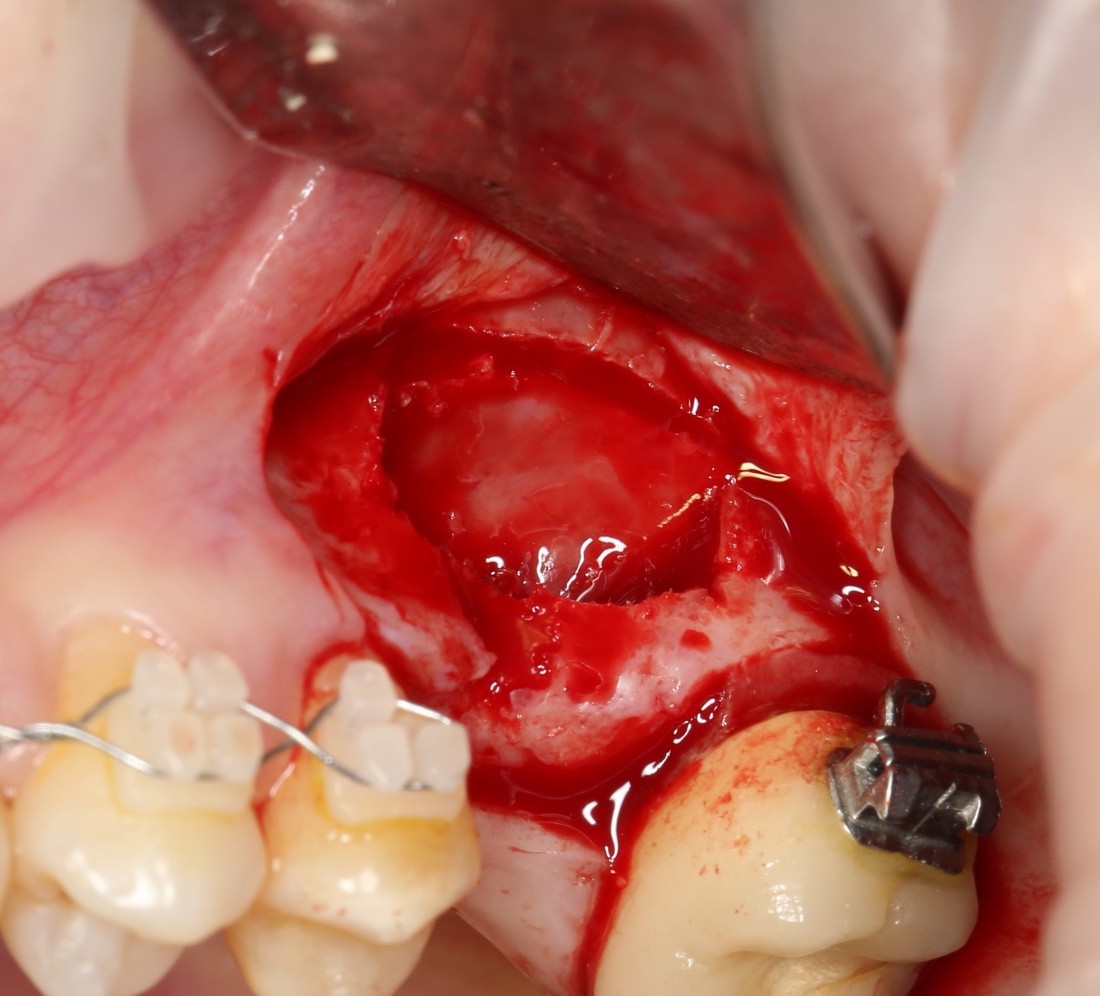

В ходе проведения операции синуслифтинга, у нас образовалась небольшая перфорация шнайдеровой мембраны:

Мы начинаем с того, что выводим ее в центр апертуры, попутно мобилизуем края. В результате, она несколько уменьшилась в размерах: